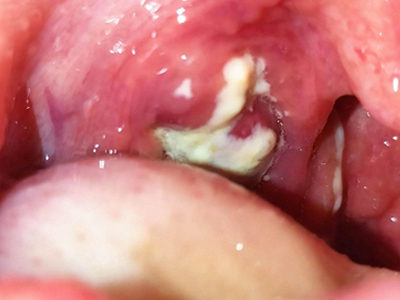

化脓性扁桃体炎一侧扁桃体多发大小不一的白斑图

化脓性扁桃体炎咽部一侧扁桃体有块状和点状白色脓性分泌物,大小差异较大,容易擦去露出红色基底面,伴有疼痛,还可能伴有高热等全身症状。